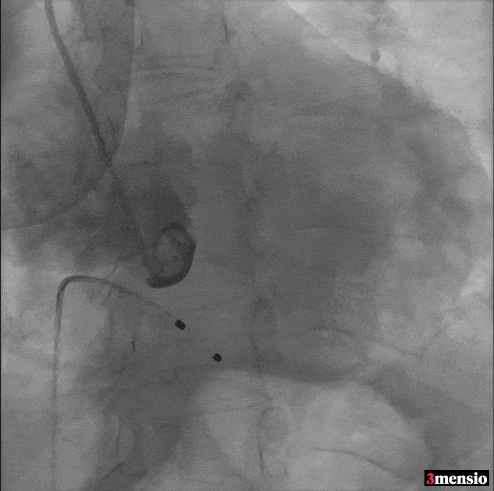

Step 1 冠状动脉造影及右窦中心造影

Step 2 瓣膜定位、释放